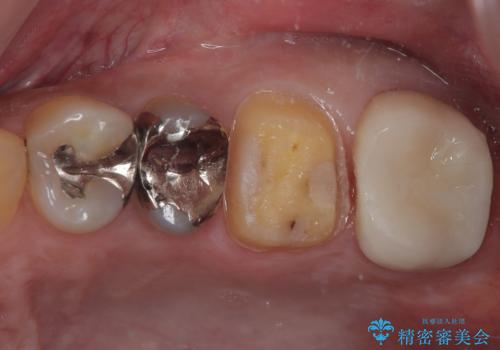

プラスチックの詰め物が外れた オールセラミッククラウン

- メインテナンス時に詰め物が外れているのでやり替えたいとのことで来院された患者様です。

以前にも詰め物が外れてオールセラミッククラウンによる補綴治療を行っており、今回も詰め物の範囲が大きい為オールセラミッククラウンによる被せもの治療を行うことになりました。

拡大鏡視野下でコンポジットレジン、虫歯を除去しオールセラミッククラウンに適した形に整えました。